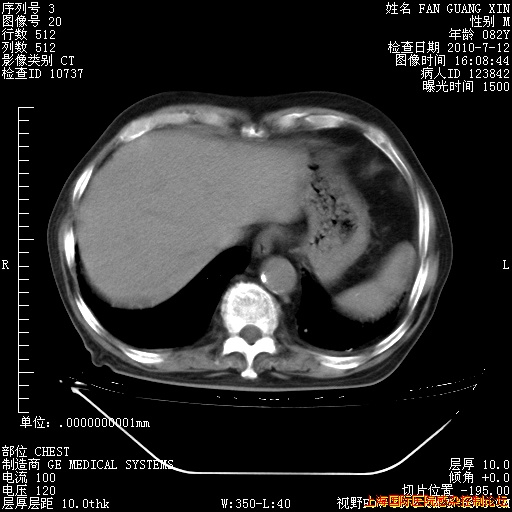

6月12日纵膈窗